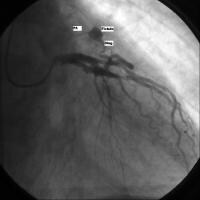

Dual LAD coronary artery[8] consists of one short and another long artery and has been classified into 4 different subtypes. In the most common form (type I), the short and long LAD coronary arteries originate from the normal LAD coronary artery proper. The shorter artery then runs in the anterior interventricular sulcus and terminates abruptly long before reaching the apex. The longer artery, however, runs on the anterior epicardial surface of the left ventricle and returns to the anterior interventricular sulcus in its distal one third and then continues on to the apex. All diagonal branches originate from the longer artery. In the type II variety, the long LAD coronary artery courses over the anterior surface of the right rather than the left ventricle.In the type III dual LAD coronary artery, the long artery has, at least partly, an intramyocardial (bridging) course. Unlike types I and II, the septal perforators arise from the long LAD and the diagonals arise from the short LAD coronary artery. Finally, in the type IV variety, the short LAD coronary artery arises from the LM coronary artery and the long artery anomalously arises from the RCA and courses to the left side anterior to the right ventricular outflow tract. Duplications of the RCA[9, 10] have been reported with both single and double ostium in the right coronary sinus. The duplicate vessels may course together in the right atrioventricular groove and/or have separate courses with one coursing on the epicardial surface of the right ventricle. Both vessels give rise to right ventricular branches and generally 1 of the 2 gives off the posterior descending coronary artery. We have recently reported duplication of the LCx[11] , or otherwise described as aberrant origin of one OM branch from the LAD, ramus intermedius, or diagonal branch of the LAD, in a case series of 24 patients. In the image below, the anomalous OM courses parallel to the LCx coronary artery and supplies blood to the acute margin of the left ventricle.